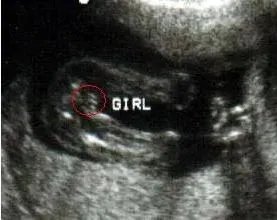

首先是女宝宝的, “三线” 是一个明显的标记: